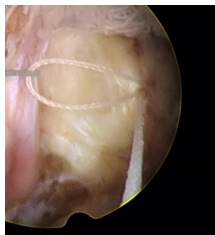

脊柱修復(fù)與重建技術(shù)之纖維環(huán)縫合術(shù)是在各種針對(duì)椎間盤突出癥的手術(shù)術(shù)式輔助下,閉合纖維環(huán)上殘留的破口,技術(shù)特點(diǎn)如下:

1、纖維環(huán)縫合手術(shù)是對(duì)椎間盤形態(tài)進(jìn)行的修復(fù),促進(jìn)了纖維環(huán)破口的愈合,是對(duì)以纖維環(huán)破裂所造成的椎間盤突出癥直接和有效的治療手段。

2、即刻閉合纖維環(huán)的破口,顯著降低椎間盤內(nèi)殘留髓核受力后從纖維環(huán)破口處再突出的復(fù)發(fā)幾率。

纖維環(huán)縫合技術(shù)是脊柱修復(fù)與重建領(lǐng)域一項(xiàng)基礎(chǔ)技術(shù),通過(guò)對(duì)突出椎間盤髓核摘除后纖維環(huán)上的破口進(jìn)行閉合處理,完成對(duì)椎間盤完整形態(tài)的修復(fù),降低椎間盤內(nèi)殘留髓核再突出的幾率,促進(jìn)纖維環(huán)愈合,對(duì)椎間盤功能的恢復(fù)具有積極影響;同時(shí),閉合的纖維環(huán)破口能夠減少盤內(nèi)炎性介質(zhì)的釋放,為重建神經(jīng)組織自然環(huán)境創(chuàng)造有利條件,從而提高患者術(shù)后生活質(zhì)量。該技術(shù)為手術(shù)治療腰椎間盤突出癥創(chuàng)造了一套更加完善的解決方案,更好的服務(wù)于患者。

適用于椎間孔鏡、椎間盤鏡、雙通道脊柱微創(chuàng)手術(shù)技術(shù)(UBE),顯微鏡、通道管等微創(chuàng)手術(shù)髓核摘除后纖維環(huán)的修復(fù),降低術(shù)后復(fù)發(fā)率